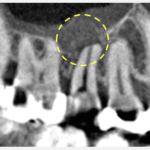

また、レントゲン画像でも、通常のレントゲン写真(上記左)だけでは根の先の骨の状態を正確に判断できません。そのため、CTによる三次元的な画像検査(上記右)も行って初めて、正しく根の先の骨の状態を把握し、歯茎が腫れて押すと痛い原因を確定することができるといえます。